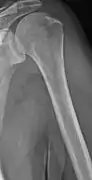

The diagnostic examination of a person with suspected multiple myeloma typically includes a skeletal survey. This is a series of X-rays of the skull, axial skeleton, and proximal long bones. Myeloma activity sometimes appears as "lytic lesions" (with local disappearance of normal bone due to resorption) or as "punched-out lesions" on the skull X-ray ("raindrop skull"). Lesions may also be sclerotic, which is seen as radiodense.[70] Overall, the radiodensity of myeloma is between −30 and 120 Hounsfield units (HU).[71] Magnetic resonance imaging is more sensitive than simple X-rays in the detection of lytic lesions, and may supersede a skeletal survey, especially when vertebral disease is suspected. Occasionally, a CT scan is performed to measure the size of soft-tissue plasmacytomas. Nuclear Medicine Bone scans are typically not of any additional value in the workup of people with myeloma (no new bone formation; lytic lesions not well visualized on nuclear bone scan).

Multiple myeloma in the upper arm

Humerus with multiple myeloma lesions

Same humerus before, with just subtle lesions